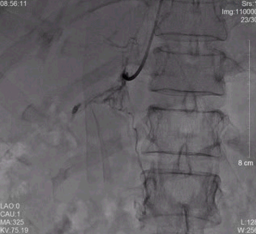

右侧、左侧肾上腺静脉取血示意图

而证明的方法,需要双侧肾上腺静脉取血术,这项微创的介入检查,仅仅国内仅少数几家医院能开展,我院就是其中之一。在充分的术前准备后,彭峰主任、方周菲和蔡瀚主治医师在介入手术室,成功为陈奶奶进行双侧肾上腺静脉取血术。取血结果证明,陈奶奶左侧肾上腺腺瘤存在大量分泌醛固酮的功能,这为手术治疗提供了最为充分且必要的证据。